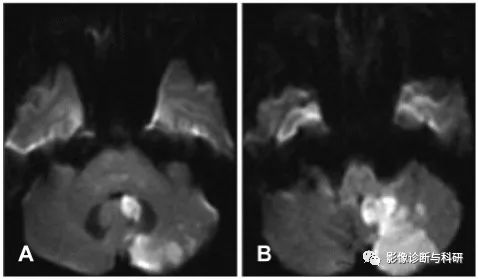

弥散加权图像显示左侧脑桥臂和左侧小脑上外侧出现急性梗塞(a)。计算机断层扫描血管造影显示左侧椎动脉狭窄和闭塞,并且双侧小脑前下动脉(AICA)缺失(b)。DSA显示左近端 AICA 闭塞(c)